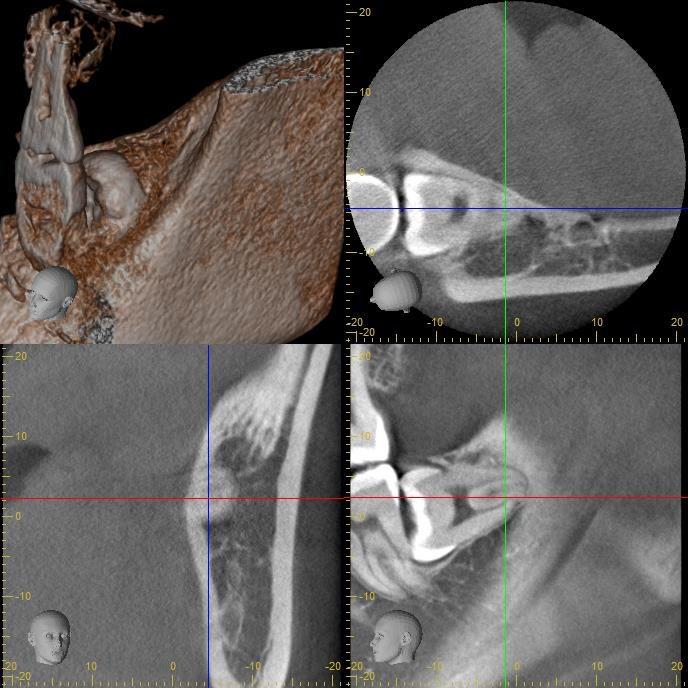

レントゲン写真の状態を御覧ください。

部位:右下8番埋伏歯

部位:左下8番埋伏歯

CT画像で状態を確認し、親知らずの歯根の曲がり具合や歯根の太さ、

下の親知らずの場合は下歯槽管神経との距離、

位置関係や骨の厚みなどを確認します。

下歯槽神経を傷をつけないように注意が必要です。

この場合、神経との距離を測り慎重に抜歯しないといけません。